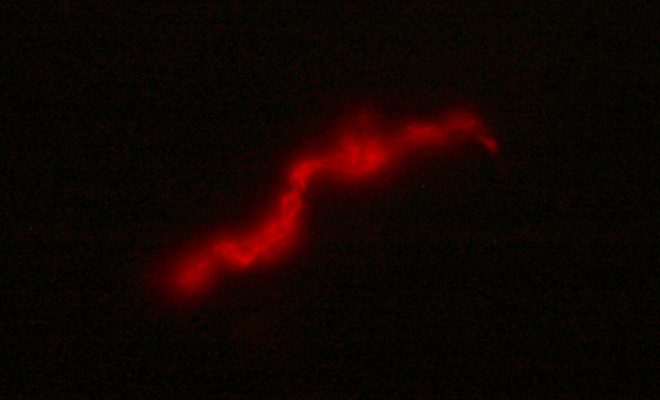

El kit FluoTB utiliza un bacteriófago que al detectar la bacteria de la tuberculosis en la muestra de esputo de un paciente produce una proteína fluorescente detectable por microscopía.

FluoTB: Test rápido y económico